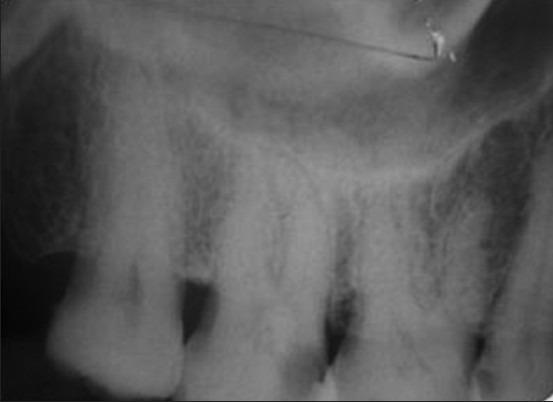

Knowledge of root canal morphology and variations is an essential factor to successful endodontic treatment. Presence of extra roots, canals, lateral canals, deltas etc., is commonly encountered. Maxillary second molar with two palatal roots or root canals is a rare dental anatomy. The purpose of this case report is to describe the successful endodontic management of a maxillary second molar with four root canals using a single reciprocating file system. The morphology is a typical characterized by two palatal roots with widely separated two orifices and canals. The tooth presented an individual mesiobuccal, distobuccal and two separate palatal roots.

了解根管形态及其变异是根管治疗成功的关键因素。额外的根、根管、侧支根管、根管袢等情况很常见。上颌第二磨牙有两个腭根或根管是一种罕见的牙齿解剖结构。本病例报告的目的是描述使用单一往复锉系统对上颌第二磨牙四个根管进行成功根管治疗的情况。其形态典型特征为两个腭根,根管口和根管广泛分离。该牙齿有一个单独的近中颊根、远中颊根和两个分开的腭根。